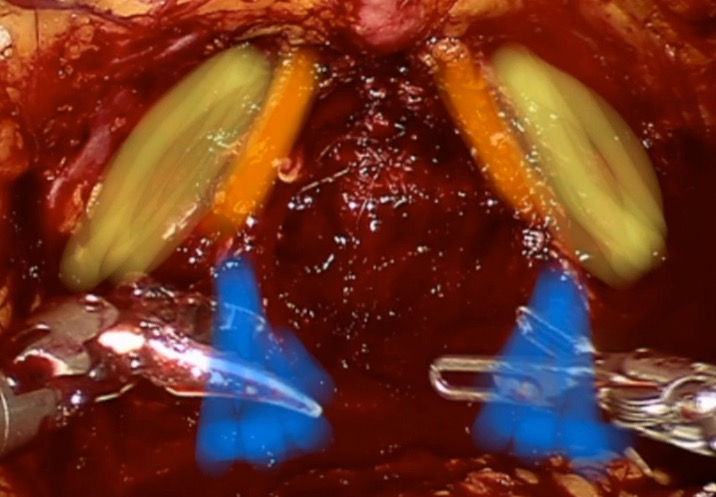

Anterior preservation can be observed below: - in yellow: the endopelvic fascia, preserved in toto - orange: arcous tendineus and pubo-prostatic ligaments - blue: proximal part of the neurovascular bundle Paper coming soon -> stay tuned @GPloussard @UroTouzani @UROSUD1